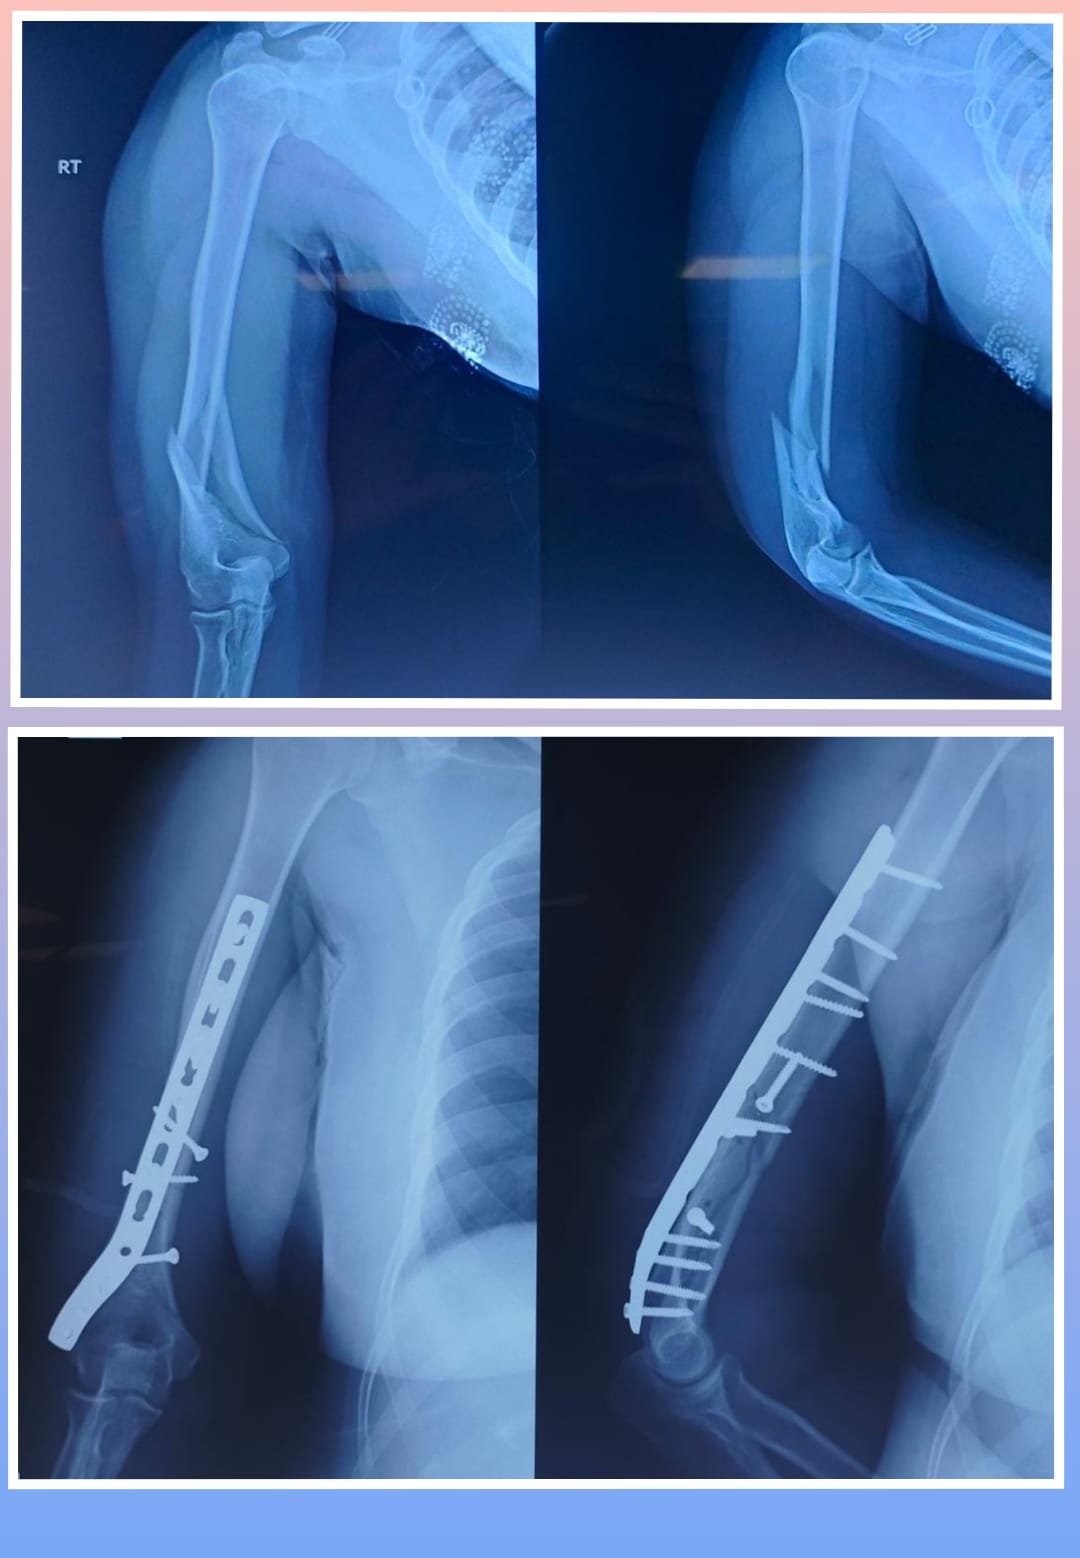

X-ray

Surgeries